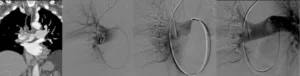

Embolia polmonare massiva: si verifica quando un trombo di grandi dimensioni occlude una delle principali arterie polmonari, determinando un episodio acuto potenzialmente letale.

Embolia polmonare submassiva: riguarda trombi di dimensioni intermedie che ostruiscono rami arteriosi più periferici, provocando una manifestazione meno grave rispetto alla forma massiva.